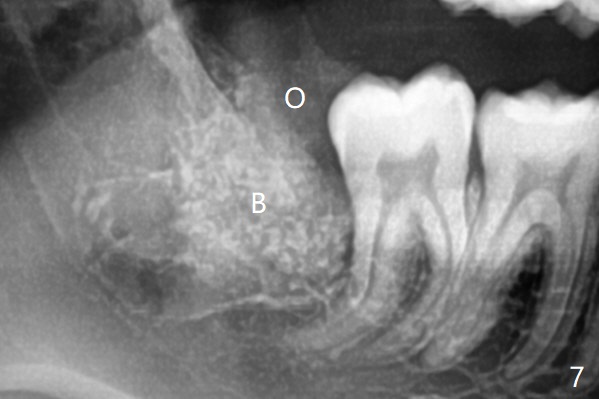

A 19-year-old man returns for #1,16,17 and 32 extraction (Fig.1,2). Because of horizontal impaction of #32 and no bone #31 distal post extraction (Fig.3 *), 3D bond (.5 cc) will be placed in the mesial socket of #32 (Fig.4 red), while Osteogen plug (1/2 (O)) in the distal one. Since there is no bony defect between #17 and 18 after extraction (Fig.5 *), a piece of Osteogen plug (cut half apical) will be inserted in #17 socket, whereas 2 small pieces of Osteogen plug placed in the apical portions (triangle and spindle shaped). Take posterior panoramic X-ray postop (bitewing type, CT format, not XV). There appears bone formation in the socket 5 months postop (Fig.10,11).

Since #32 sockets seem large, extending mesiobuccal (Fig.6), Bond Apatite (1 cc) is placed instead (Fig.7 B), covered by 1/3 of Osteogen plug (O) and sutured with 4-0 PGA. Extraction of #17 is also difficult. As 2 sockets are indistinct, a piece of Osteogen plug with split is placed (Fig.8) upside down (Fig.9 vs. Fig.5). There appears bone formation in the socket 5 months postop (Fig.10,11).